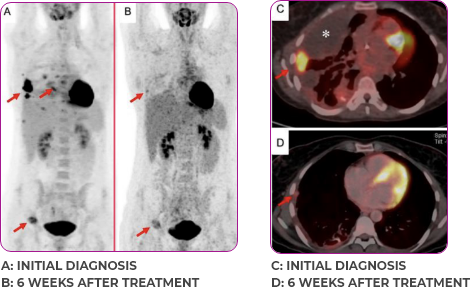

PATIENT CASE:

METASTATIC NSCLC1,a

- PRa after 6 weeks of treatment with VITRAKVI® (larotrectinib)

- Complete clinical response achieved by 12 months with residual scarring

Response to VITRAKVI1

- Partial response and symptom improvement confirmed by chest X-rays after <1 month of treatment

- Imaging performed 6 weeks into treatment revealed considerable decrease in the size of both target lesions

- Patient was symptom free and remained on VITRAKVI

Response in primary and metastatic lesions1

Lung imaging of primary tumors.

SCAN 1: LUNG

SCAN 2: LUNG AND BONE